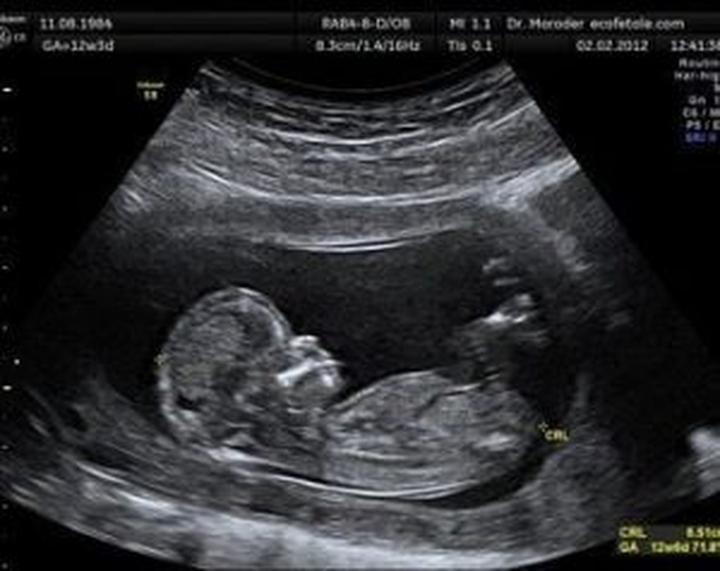

Ultrasonografia, szeroko znana jako USG, stanowi nieodłączny element życia ciężarnych kobiet, które nie wyobrażają sobie bez niej codzienności. Ta metoda diagnostyczna nie tylko skutecznie wykrywa ewentualne zagrożenia, ale również buduje silną emocjonalną więź pomiędzy rodzicami a ich pociechą. Czy jednak można mieć jakiekolwiek obawy? Badania naukowe wyraźnie pokazują, że nie ma się czego bać! Przez cztery dekady stosowania USG u kobiet w ciąży nie odnotowano praktycznie żadnych negatywnych skutków dla rozwijających się płodów. Tak samo jak Piotruś (później, w brzuszku mamy, trochę się porusza), tak aparaty USG radzą sobie z obrazowaniem, a ich moc pozostaje ograniczona do absolutnego minimum.

Chcąc uspokoić serca matek, które zadają sobie pytanie: „A co, jeśli to jednak szkodzi?”, warto przytoczyć zalecenia Światowej Organizacji Ultrasonografii w Medycynie i Biologii. Eksperci podkreślają, że ryzyko szkodliwego wpływu rutynowego badania w pierwszym trymestrze ciąży jest minimalne. Naukowcy przeanalizowali dwa główne mechanizmy działania – termiczny i kawitacyjny. Jeśli jednak podczas badania zastosujemy technologię dopplerowską, zaleca się zachowanie ostrożności w pierwszym trymestrze, ponieważ może ona podnieść temperaturę ciała o 1,5°C. W takich momentach lepiej skupić się na podglądaniu malucha na monitorze, zamiast nasłuchiwać jego dźwięków!

Badanie USG ma na celu wczesne wykrycie wszelkich nieprawidłowości rozwojowych, co da lekarzowi szansę na szybkie podjęcie ewentualnych działań. Każde z trzech głównych badań USG zaplanowane jest z myślą o danym etapie ciąży: od potwierdzenia bicia serca w pierwszym trymestrze, przez szczegółowe sprawdzenie anatomii w drugim, aż po ocenę wzrostu i położenia płodu tuż przed porodem. To trochę jak układanie puzzli, gdzie każdy kawałek jest równie ważny, a USG pomaga w ich połączeniu, zwłaszcza gdy chodzi o zdrowie maluszka!